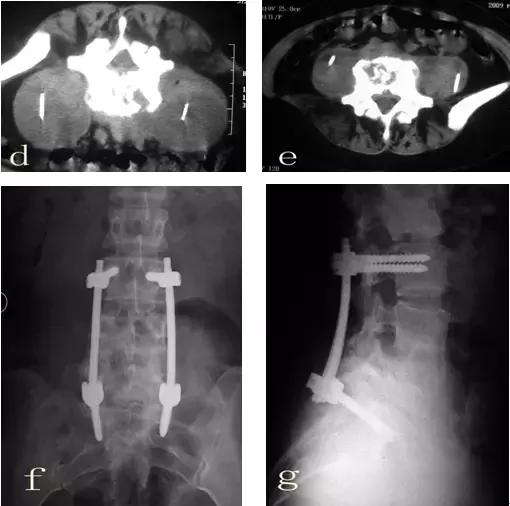

患者郭某,女性,25岁。因腰痛一年余,曾经在多家医院就诊,诊断为腰椎间盘突出,给予对症治疗,当时有所减轻,近来腰痛加重,经检查后考虑腰椎结核而到我院就诊。查体:脊柱向右侧弯曲,L4-5棘间压痛,叩击痛。左侧腹股沟区可触及100px×125px包块,触之波动感。实验室检查:血清抗结核阳性,血沉69mm/h,C-反应蛋白164.9mg/dl,PPD试验强阳性。腰椎平片(图a)示:腰4/5间隙变窄,L4椎体上缘骨质破坏。腰椎CT(图b)示:L4、L5椎体骨质有破坏,并有死骨形成,双侧腰大肌内可见液性暗区。腰椎MRI(图c)示:椎间盘等T1略短T2信号,临近骨组织呈长T1长T2信号,正常椎间盘信号消失,L4椎体下半部分L5上半部分骨质破坏,周围软组织肿胀,腰椎双侧腰大肌及骶前脓肿形成。入院诊断:腰椎结核(L4/5),腰大肌脓肿(双侧),骶前脓肿。入院后给予H.R.Z.E初治方案,同时在CT引导下行双侧腰大肌脓肿穿刺置管引流术(图d),引流后病人症状明显缓解,血沉(36mm/h)、C-反应蛋白(97.9mg/dl)明显下降,复查腰椎CT(图e)脓肿明显减少,经过抗结核治疗四周后给予行后路椎弓根钉棒系统内固定、前路病灶清除取髂骨植骨融合术(图f、g)。

该病例为腰椎结核的典型病例,具有腰椎结核的典型表现,包括血沉增快、C-反应蛋白升高、血清抗结核抗体阳性、PPD试验阳性、椎体破坏、死骨形成、腰大肌脓肿、椎旁脓肿、流注脓肿等,诊断明确。由于脓肿较大,结核中毒症状重,没有进行抗结核药物治疗,首先采用微创手术将脓液引流减少毒素吸收,进行规范抗结核药物治疗后再进行手术治疗。由于近几年脊柱外科的发展及相关的基础研究证实脊柱结核病灶内可以一期植入内固定材料,所以现在病灶清除植骨内固定术逐渐成为现代脊柱结核治疗的标准术式。

在规范的抗结核药物治疗的支持下应当对具有手术指征的病人进行手术治疗。手术治疗目的:病灶清除、神经减压、矫正畸形、植骨融合、脊柱稳定,最终使脊柱结核达到治愈。病灶清除的范围不宜将病椎整体切除,应当对L4椎体下把部分L5椎体上半部分进行部分切除,尽可能保留健康的椎体,融合的范围应当越小越好,尽量只融合受到破坏的脊柱功能单位,即只对L4/5椎间融合。

腰椎结核尤其在腰骶部的椎体破坏,前路内固定比较困难,可以选择后路内固定,前路经腹膜外病灶清除术,这样可以使病人早期下床,提高植骨融合率,缩短病人的康复时间。前路脊柱融合应当只融合已经破坏的节段(L4/5),待植骨块融合、结核治愈后取出内固定,可以尽可能多的恢复腰椎功能单位,可以减少临近腰椎间盘退变的几率。